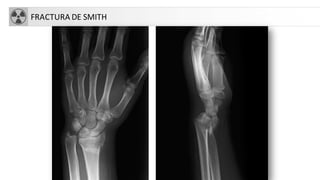

FRACTURASDE MUÑECA

• 17% de fracturas atendidas en urgencias (1/4 del total de

fracturas)

• Más frecuente mujeres y osteoporosis

• FX Colles. Criterio: fractura de extremo distal de radio con

angulación dorsal y acortamiento radial, que produce la

típica deformidad en dorso de tenedor

• FX extremidad distal de radio (si no cumple criterios

anteriores).

• Otras FX: Smith, Barton, Hutchinson…

• Genéricamente: FX EDR

FRACTURA DE SMITH